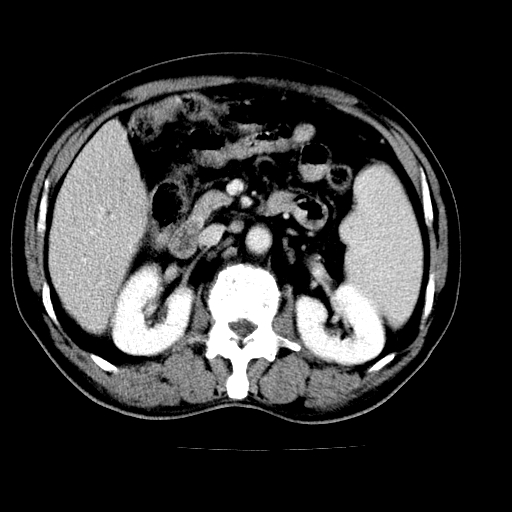

男,66岁,上腹部不适、黄染一周。彩超示:肝左叶占位,肝内胆管扩张,胆总管扩张,胆总管占位?

肝左叶占位性病变,并胆管扩张,符合胆管细胞癌ct表现,门脉左支受累,左肾囊肿。窗宽太窄了,其他的看不清

左叶胆管细胞癌累及胆总管,门脉左支受侵,慢性胆囊炎胆结石,左肾小囊肿